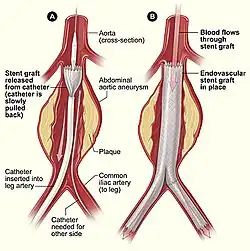

A stent graft or covered stent is type of vascular stent with a fabric coating that creates a contained tube but is expandable like a bare metal stent. Covered stents are used in endovascular surgical procedures such as endovascular aneurysm repair. Stent grafts are also used to treat stenoses in vascular grafts and fistulas used for hemodialysis.

Vascular stents are commonly used in angioplasty, a surgical procedure that opens blocked arteries and places a stent to keep the artery open. This is a common treatment for heart attacks and is also used in the prevention and treatment of strokes. Over 2 million people receive a stent each year for coronary artery disease alone. Vascular stents can also be used to prevent the rupture of aneurysms in the brain, aorta, or other blood vessels.[6][7]